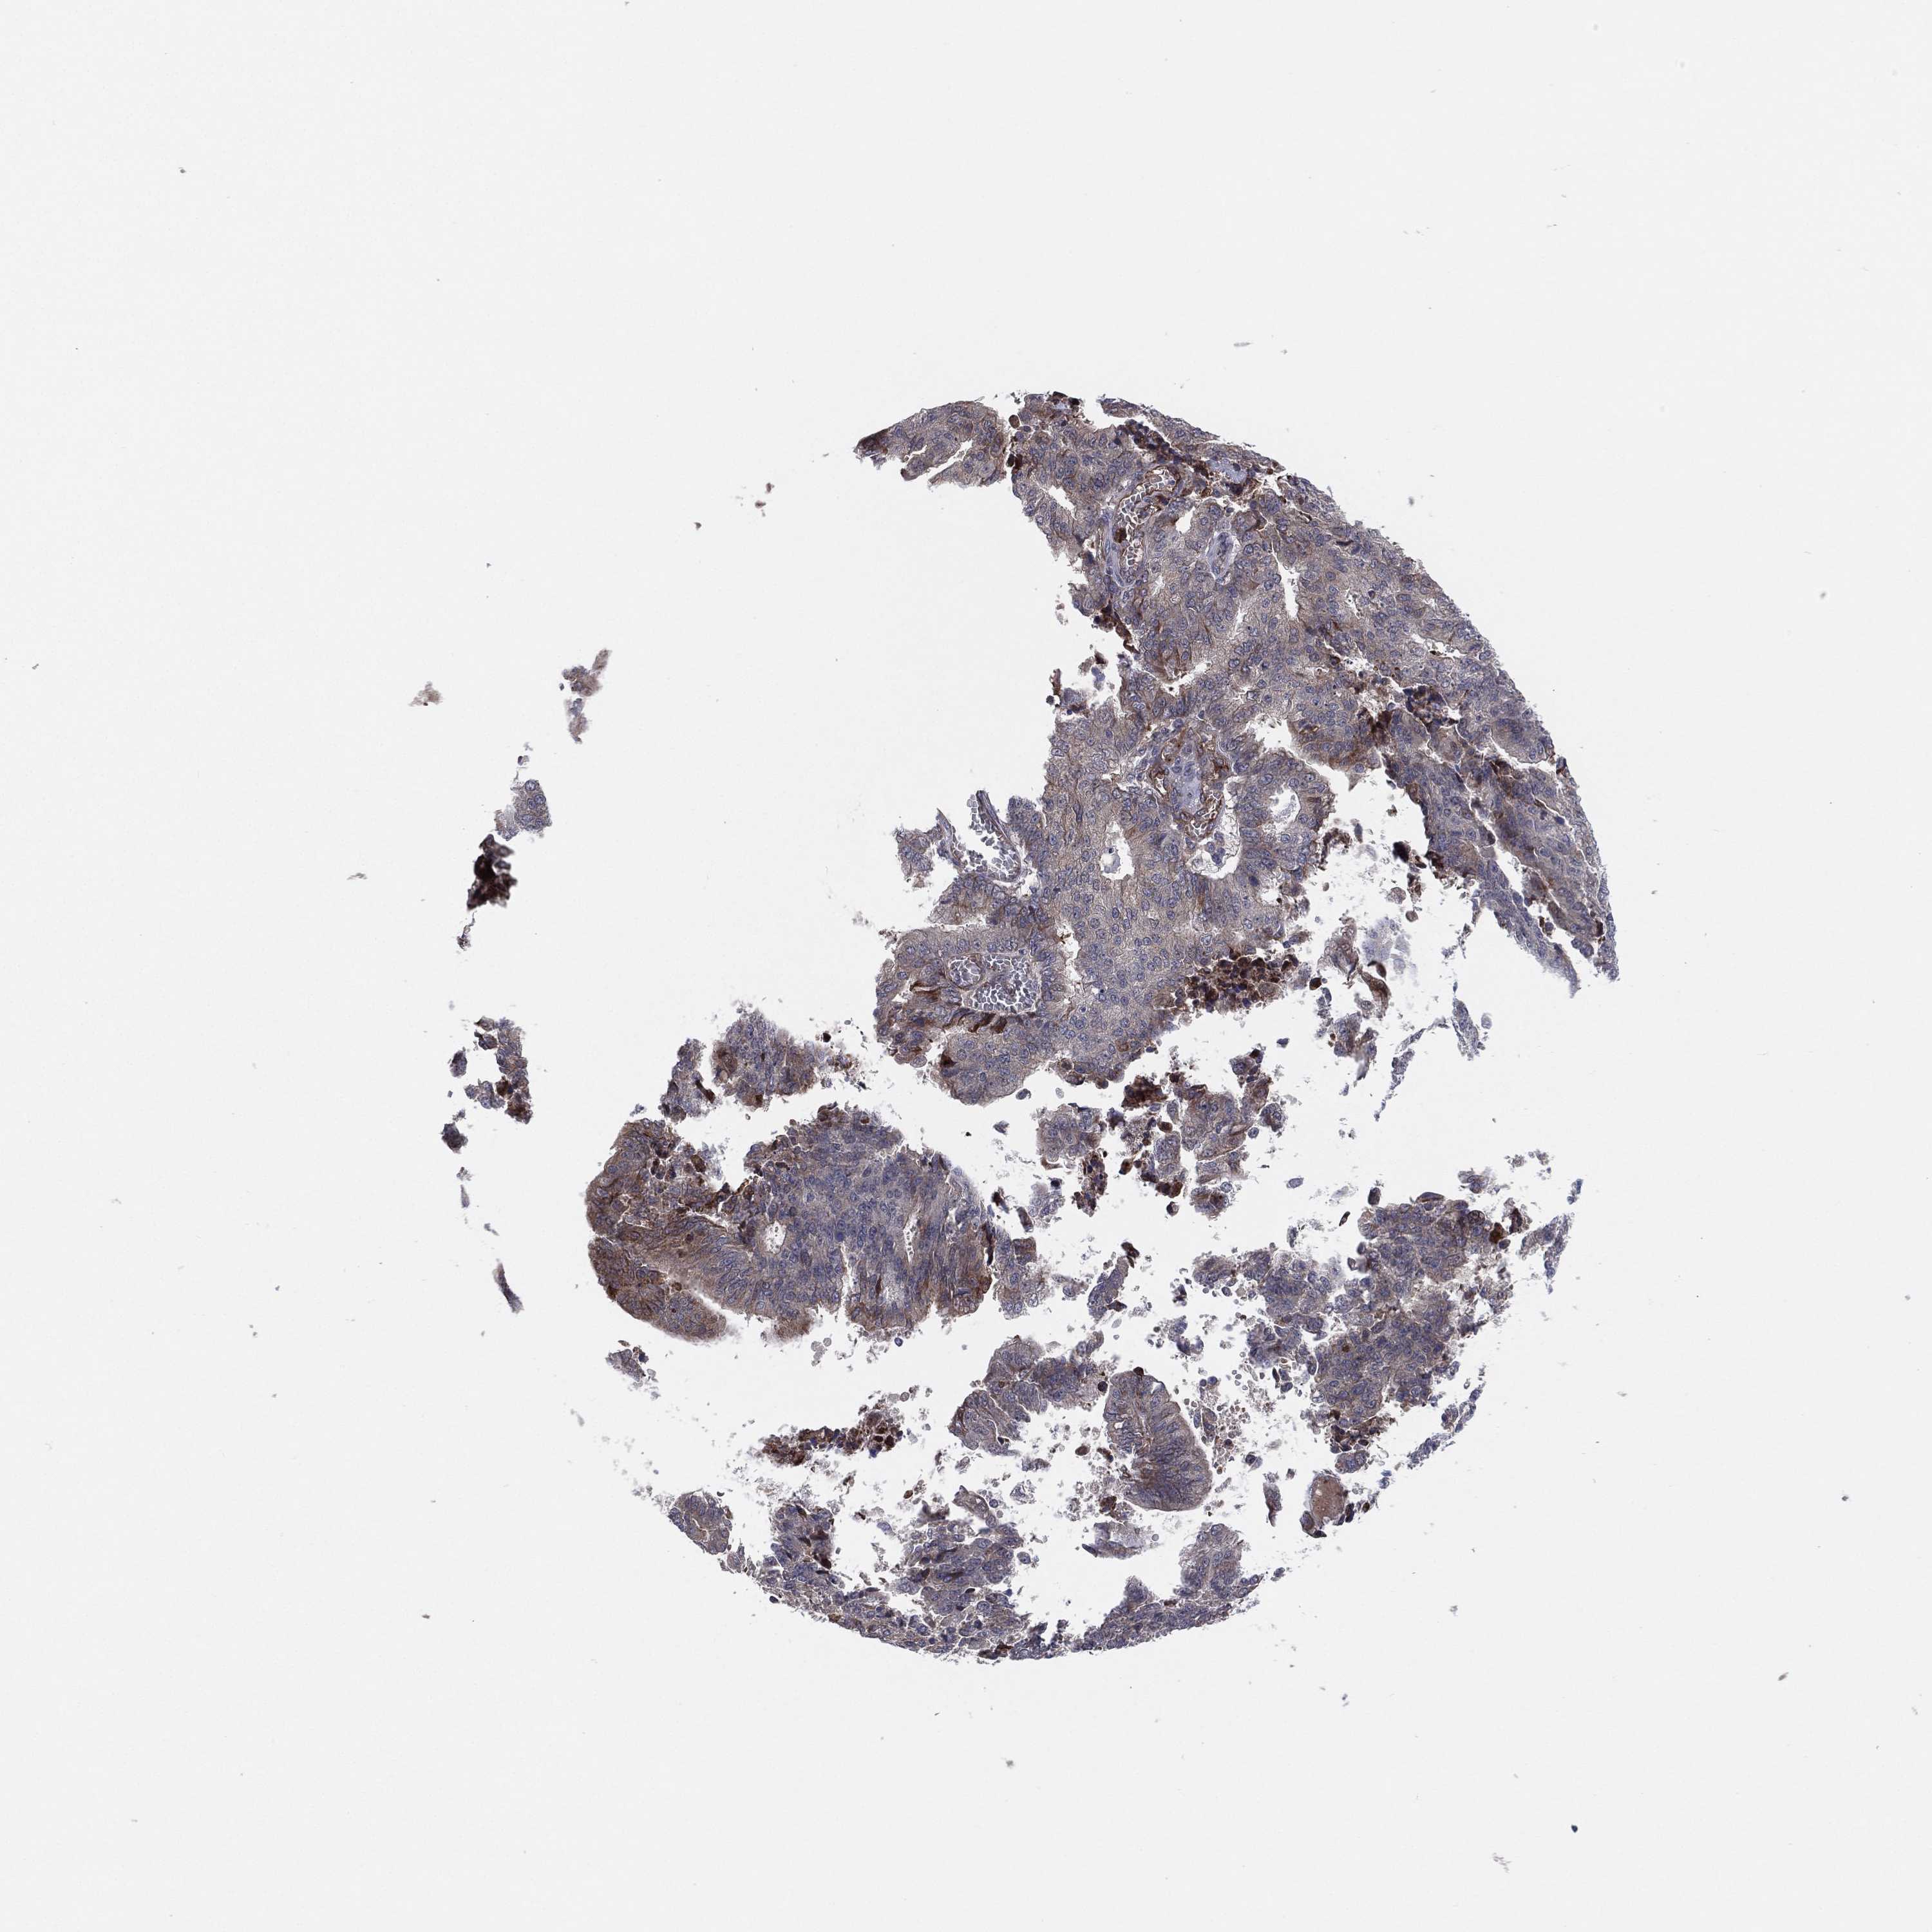

ENDOMETRIAL CANCER - Protein expressioni

A mouse-over function shows sample information and annotation data. Click on an image to view it in a full screen mode. Samples can be filtered based on level of antibody staining by selecting one or several of the following categories: high, medium, low and not detected. The assay and annotation is described here.

Note that samples used for immunohistochemistry by the Human Protein Atlas do not correspond to samples in the TCGA dataset.

Antibody stainingi

Antibody staining in the annotated cell types in the current human tissue is reported as not detected, low, medium, or high, based on conventional immunohistochemistry profiling in selected tissues. This score is based on the combination of the staining intensity and fraction of stained cells.

Each image is clickable and will lead to virtual microscopy that enables deeper exploration of all samples and also displays staining intensity scores, fraction scores and subcellular localization as well as patient and tissue information for each sample.

Antibody HPA047217

Antibody HPA054023

Antibody CAB079950

Staining

High

Medium

Low

Not detected

Intensity

Strong

Moderate

Weak

Negative

Quantity

>75%

75%-25%

<25%

None

Location

Nuclear

Cytoplasmic/membranous

Cytoplasmic/membranous,nuclear

Adenocarcinoma, NOS